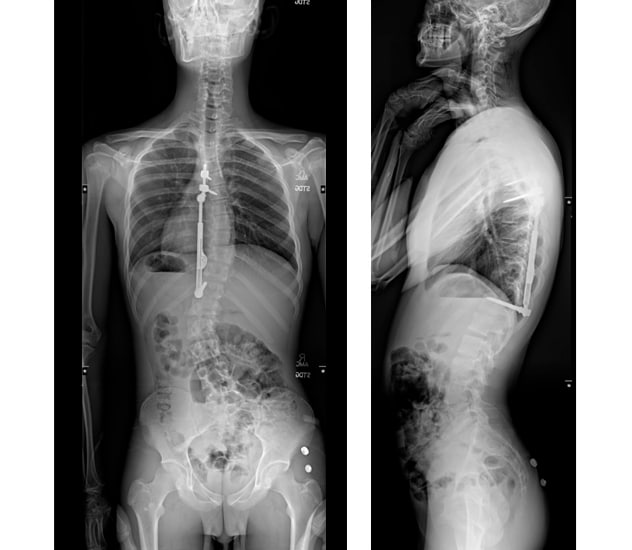

Preoperative curve and postoperative correction

Case example shows preoperative curve, immediate postoperative correction and ongoing correction over time as the child grows. Approximately 20 degrees of front-to-back position and 10 degrees of side-to-side motion are maintained after VBT surgery, and normal anatomy is preserved.